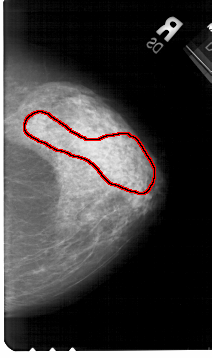

FILE: A_1511_1.RIGHT_MLO.OVERLAY

TOTAL_ABNORMALITIES 1

ABNORMALITY 1

LESION_TYPE CALCIFICATION TYPE AMORPHOUS DISTRIBUTION SEGMENTAL

ASSESSMENT 4

SUBTLETY 3

PATHOLOGY BENIGN

TOTAL_OUTLINES 1

BOUNDARY